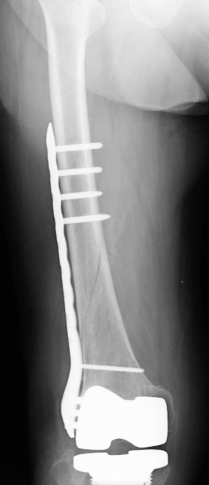

人工膝関節置換術の内容は、傷ついてしまった膝の軟骨や骨を表面的に切り取り、膝の変形を矯正し、金属やセラミック、ポリエチレンなどでできた人工関節に置き換える手術です。手術は1時間程度で終わります。膝がとても痛くて、変形性膝関節症の方やリウマチの方が手術の適応になります。

人工膝関節置換術の手術は、膝痛が消失し歩行能力が改善するというメリットがある反面、いくつかの合併症が伴うことも事実です。そのため、それぞれの合併症に対する予防策をとることがとても大切です。対策を十分とることによって、手術後のリスクを軽減することが可能です。今回の動画を通して、人工膝関節置換術の後に注意すべき合併症について理解していきましょう。